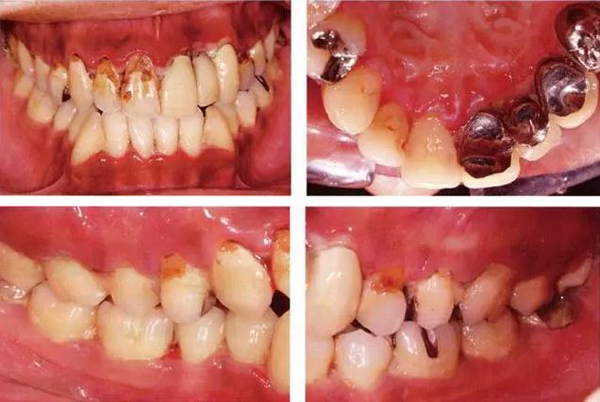

●33歲男性 侵襲性牙周炎廣泛型口腔內(nèi)照片

33歲男性,吸煙(1天10根,12年吸煙史)。菌斑控制狀況不好,牙周探診全頜牙周袋深5~10mm之外,全頜性牙周袋出血,部分牙周袋有排膿現(xiàn)象。X片可觀察到全頜性重度骨吸收。通過(guò)以上檢查可診斷出該患者為侵襲性牙周炎廣泛型。視診可知牙齦雖然有炎癥,但沒(méi)有出現(xiàn)嚴(yán)重浮腫,沒(méi)有大量牙結(jié)石沉積。